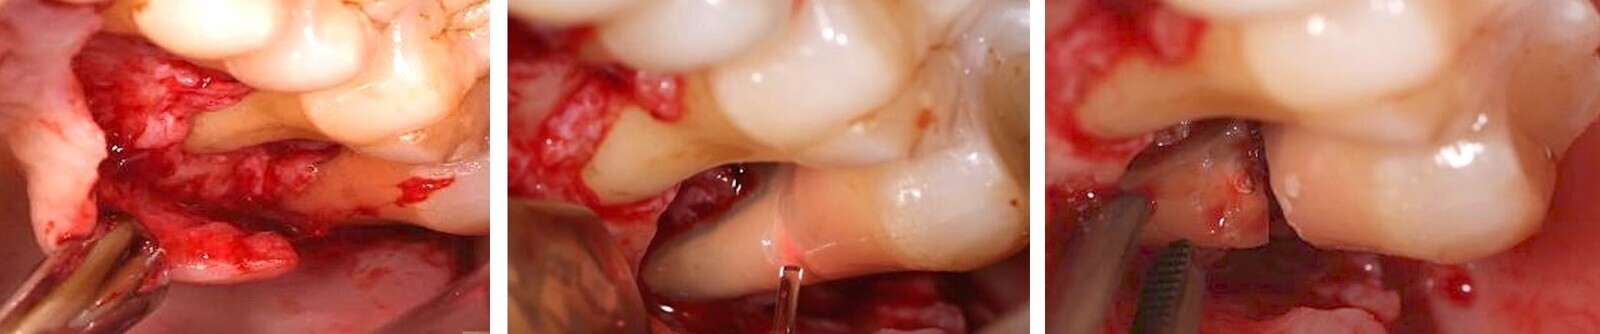

Algunos láseres como los de erbio, y en mi día a día en concreto el de Er,Cr:YSGG (Waterlase), permiten realizar un corte óseo quirúrgico muy preciso (Figuras 9-13), que transmite un daño térmico mínimo a los tejidos adyacentes9.

El láser Er,Cr:YSGG de alta potencia permite realizar cortes óseos quirúrgicos muy precisos (ver Figuras 9-13).

Figura 9.

Figura 10.

Figura 11.

Figura 12.

Figura 13. Las figuras 9-13 permiten observar un corte óseo quirúrgico muy preciso realizado con láser de erbio que produce un daño térmico mínimo en los tejidos adyacentes.